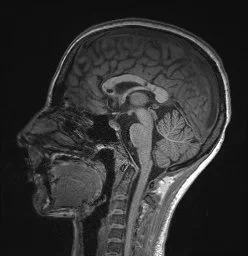

• Lesions affect roof and central fibers of corpus callosum.

• Note: MS lesions typically involve the callososeptal interface (first picture) and extend up into the callosal substance.

• Callososeptal interface: inferior surface of the corpus callosum, where the septum pellucidum abuts it.